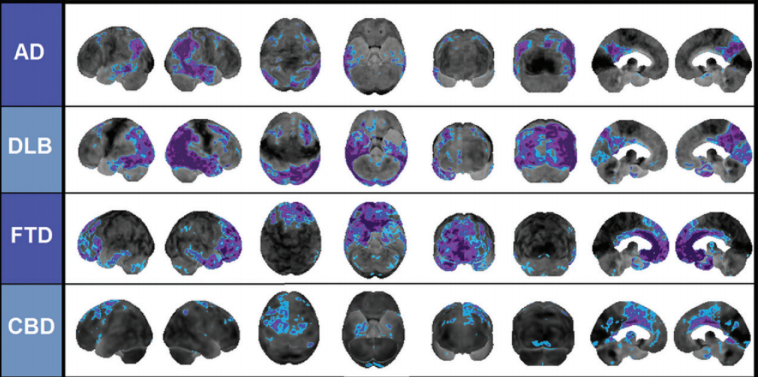

Alzheimer disease

lewy body dementia

frontotemporal dementia

corticobasal degeneration